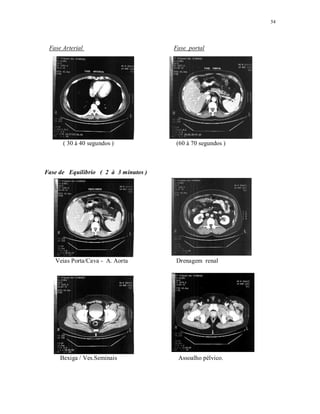

Fase Arterial Fase portal

( 30 à 40 segundos ) (60 à 70 segundos )

Fase de Equilibrio ( 2 à 3 minutos )

Veias Porta/Cava - A. Aorta Drenagem renal

Bexiga / Ves.Seminais Assoalho pélvico.